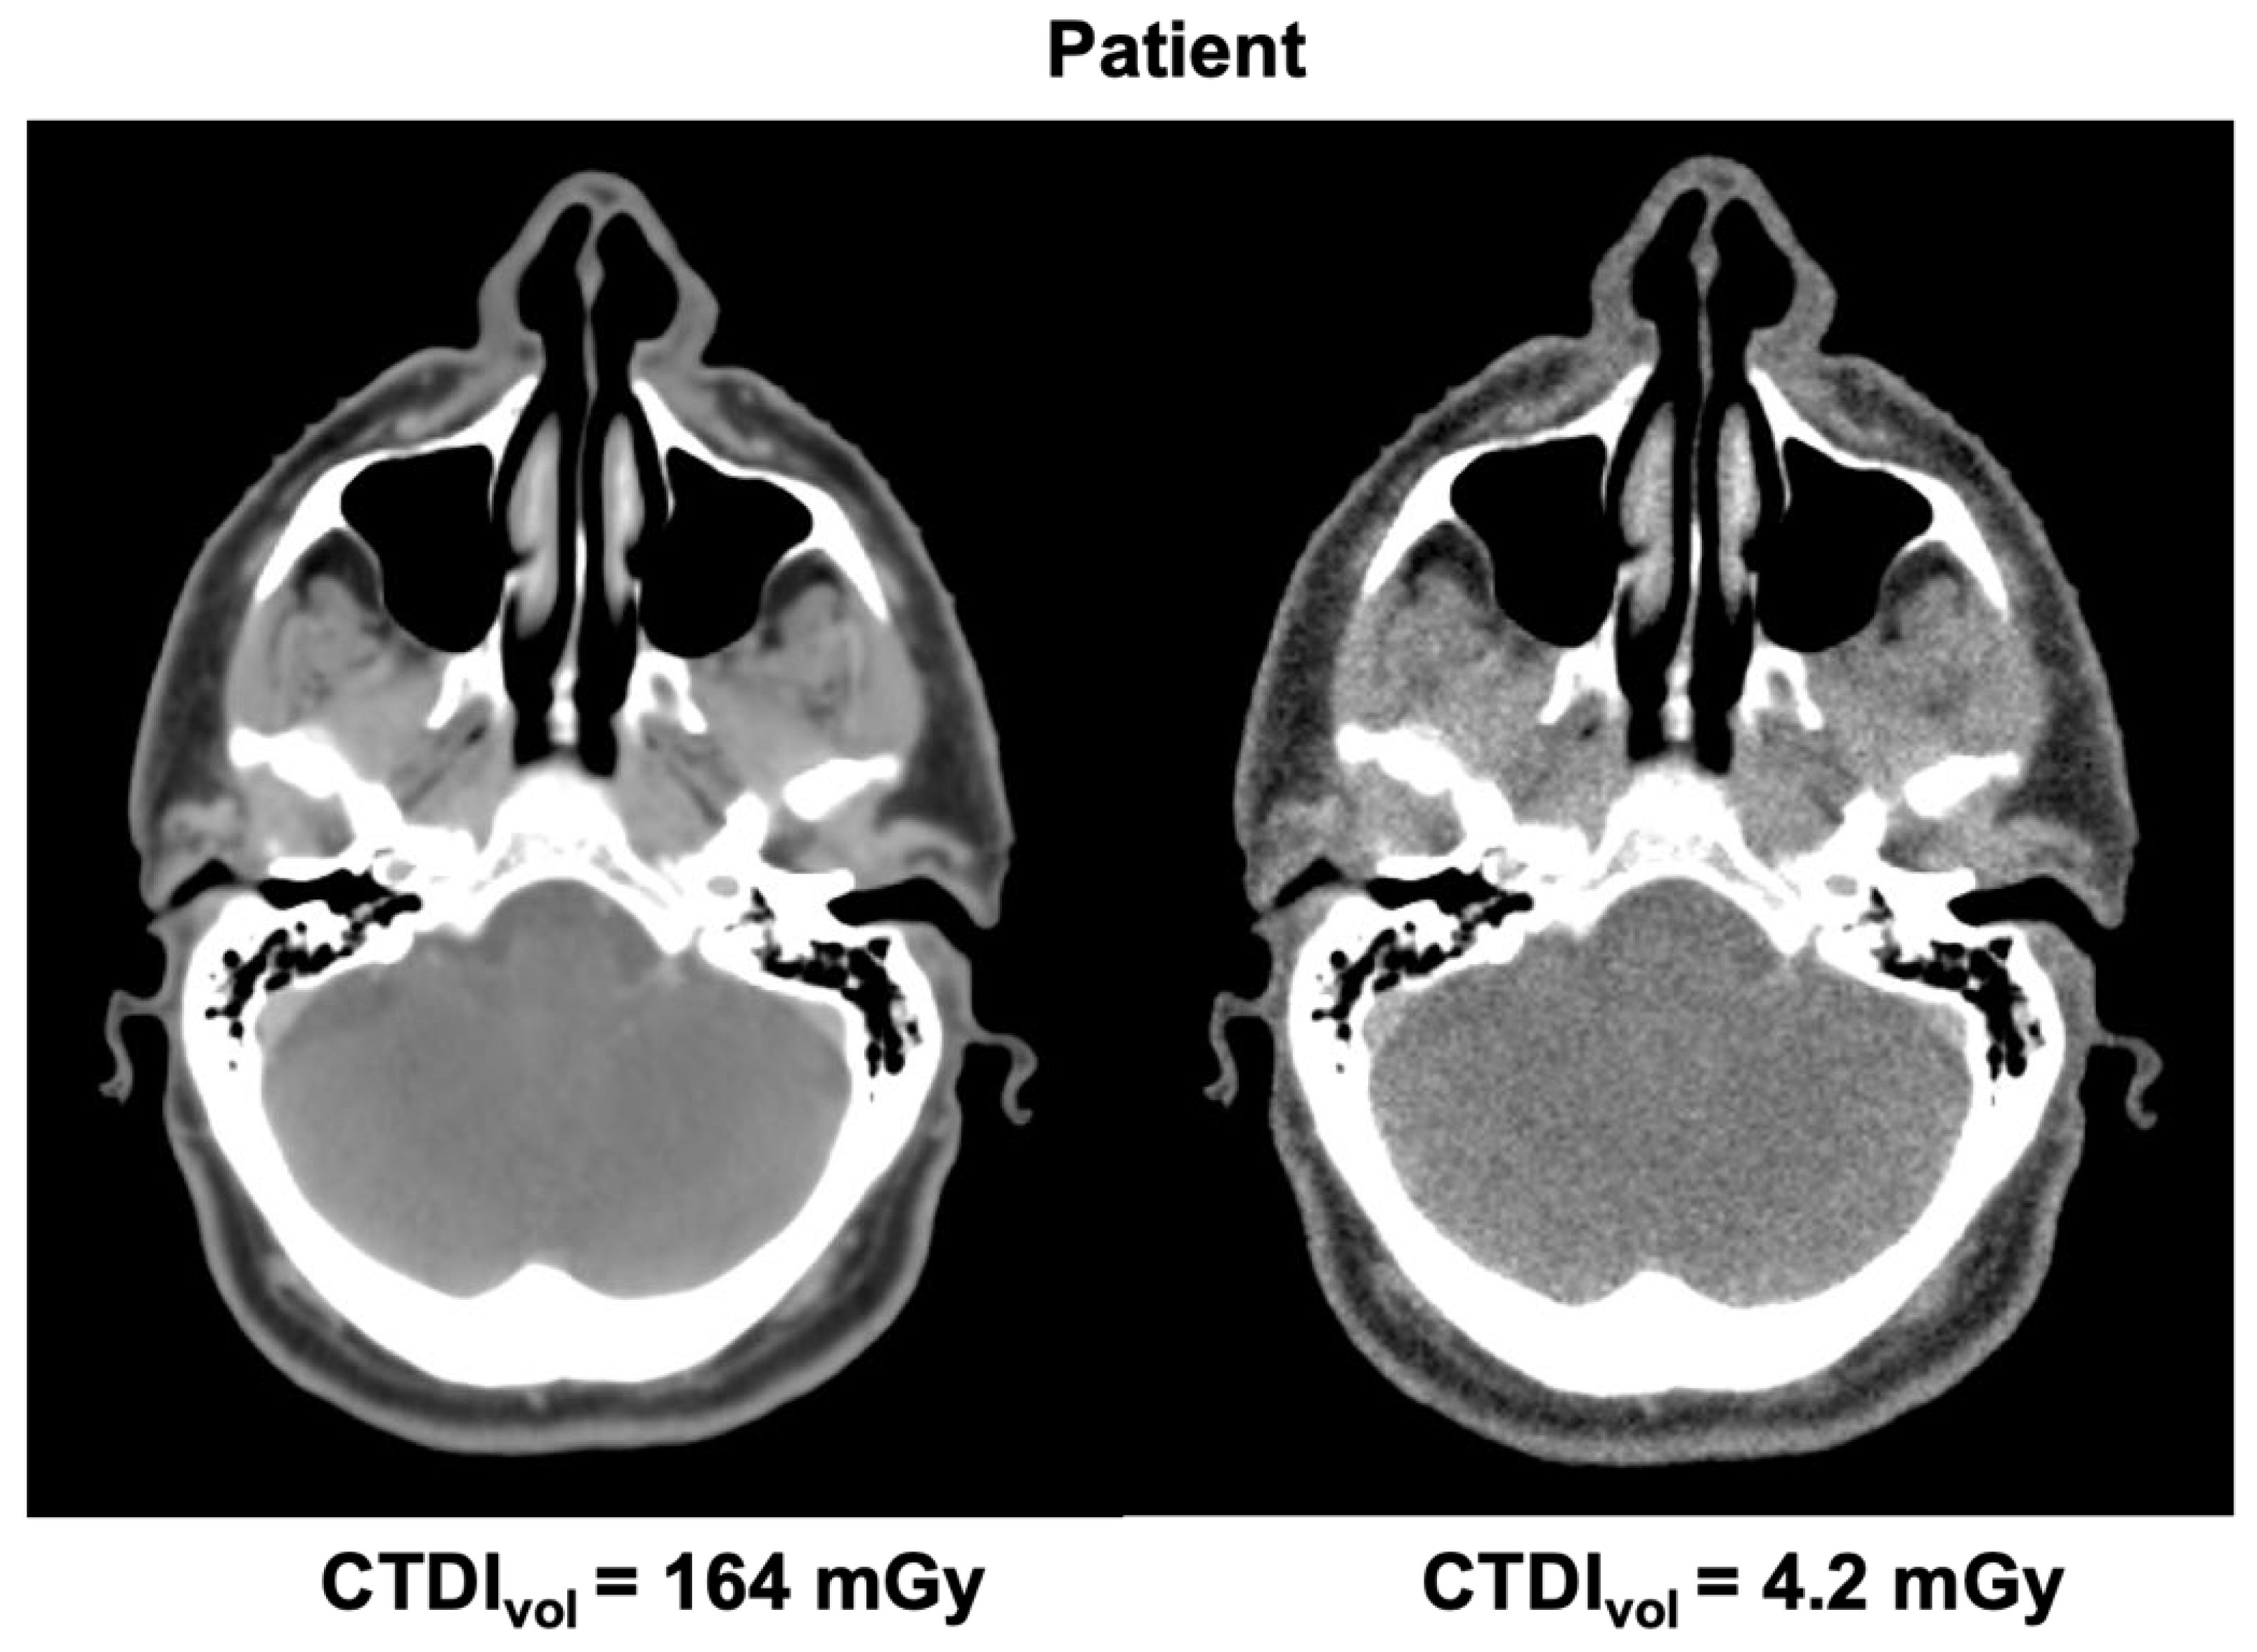

| Tube Current | CTDIvol | Tube Voltage | Pitch Factor | Slice Thickness |

|---|---|---|---|---|

| 400 mA (STD) | 166 mGy | 140 kV | 0.6 | 2.5 mm |

| 200 mA | 83 mGy | 140 kV | 0.6 | 2.5 mm |

| 100 mA | 41.5 mGy | 140 kV | 0.6 | 2.5 mm |

| 50 mA | 20.7 mGy | 140 kV | 0.6 | 2.5 mm |

| 25 mA | 10.4 mGy | 140 kV | 0.6 | 2.5 mm |

| 15 mA | 6.2 mGy | 140 kV | 0.6 | 2.5 mm |

| 10 mA | 4.2 mGy | 140 kV | 0.6 | 2.5 mm |